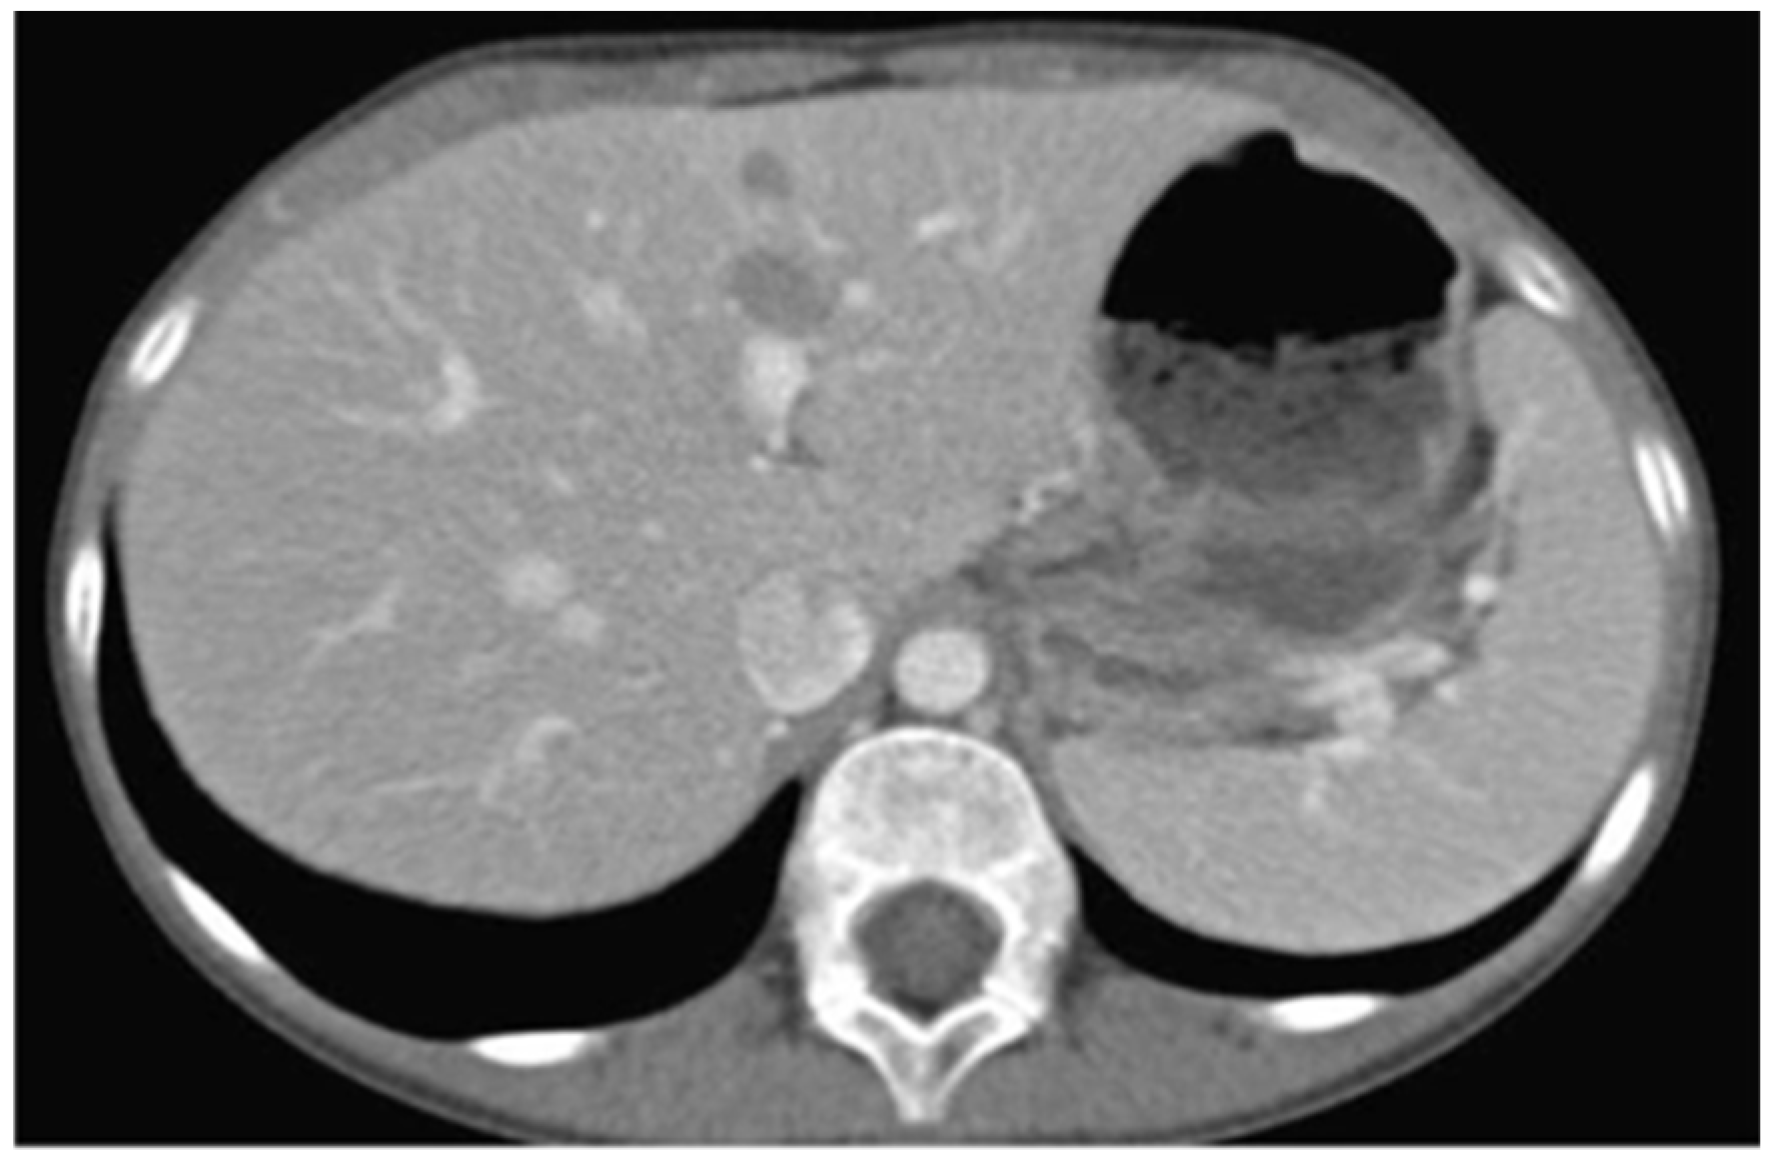

| 44 | Papadopoulou et al., 2024 (present case) | 11 | F | Painful swellings of the gingiva of the lower molars, tooth hypermobility, and facial asymmetry | Bilateral gingival swellings (erythematous and focally ulcerated) adjacent to mandibular premolars and molars that were hypermobile, displaced, and partially extruded Facial swelling along the right posterior mandible | Panoramic radiograph: ill-defined radiolucencies in the posterior mandible bilaterally, ‘floating-in-air’ teeth appearance CT: hypodense masses along and distal to the mandibular ramus extending upwards into the maxillary sinuses bilaterally, and the posterior wall of the right orbit; perforation of the right mandibular cortex | 11 years, no recurrence |